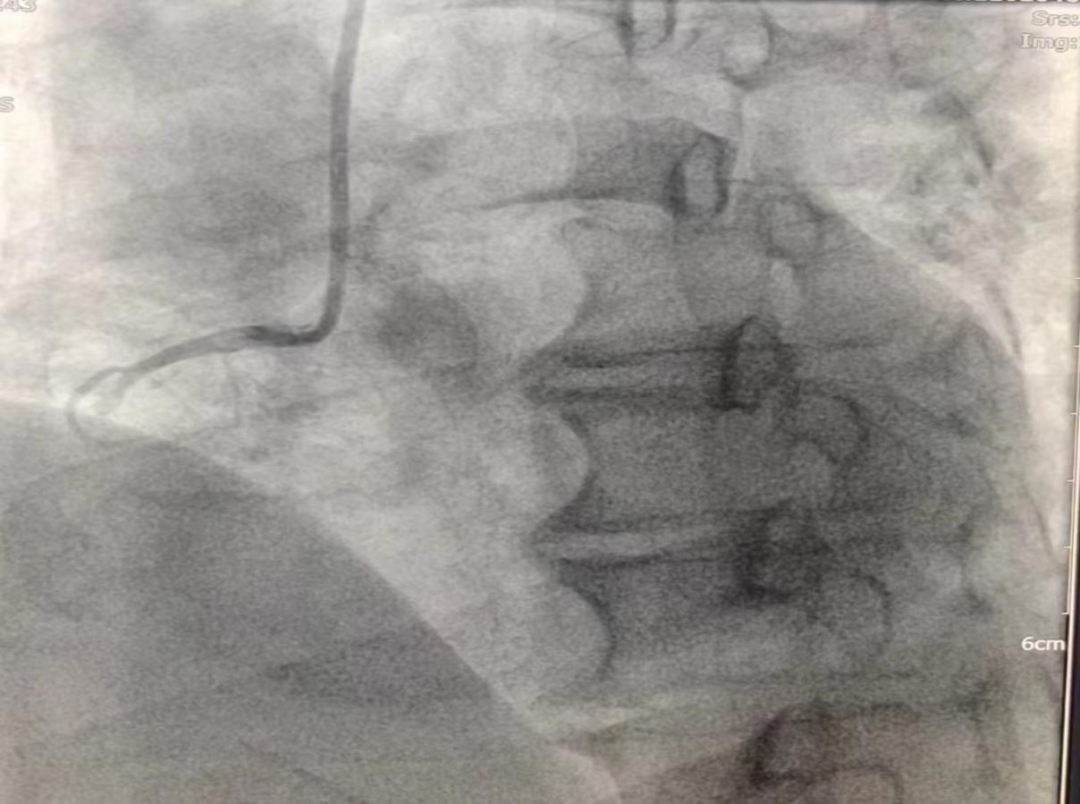

女性患者,49歲,突發(fā)暈厥急診我院,經(jīng)診斷為:冠狀動(dòng)脈粥樣硬化性心臟病、2型糖尿病。導(dǎo)入造影導(dǎo)管行冠狀動(dòng)脈造影示:冠狀動(dòng)脈分布呈左冠優(yōu)勢(shì)型,LM未見明顯狹窄,血流TIMI3級(jí);LAD全程多發(fā)斑塊,中段狹窄約60%,遠(yuǎn)端狹窄約50%,D1未見明顯狹窄,血流TIMI3級(jí);LCX未見明顯狹窄,血流TIMI3級(jí),RCA近端狹窄約50%,中段發(fā)出圓錐支后完全閉塞,血流TIMI0級(jí),急診開通血管并充分?jǐn)U張,殘余狹窄仍然嚴(yán)重。在與患者及家屬溝通時(shí),其了解得知臨床有一種新型的可吸收支架,植入體內(nèi)后支架能完全被降解和吸收,希望能用這種新型的支架進(jìn)行手術(shù)治療。由于生物可吸收支架有著嚴(yán)格的適應(yīng)癥,因此經(jīng)過嚴(yán)格篩選評(píng)估,最終對(duì)患者進(jìn)行了Xinsorb生物可吸收支架置入術(shù)。支架植入術(shù)前經(jīng)過充分預(yù)擴(kuò)張,按照規(guī)范的可吸收支架操作流程,快速送入可吸收支架到病變部位,精準(zhǔn)定位后14個(gè)大氣壓釋放,生物可吸收支架后擴(kuò)球囊擴(kuò)張。充分球囊后擴(kuò)張,以保證支架貼壁良好,血流速度正常,造影完美,手術(shù)順利結(jié)束。

(圖為右冠病變術(shù)前影像)